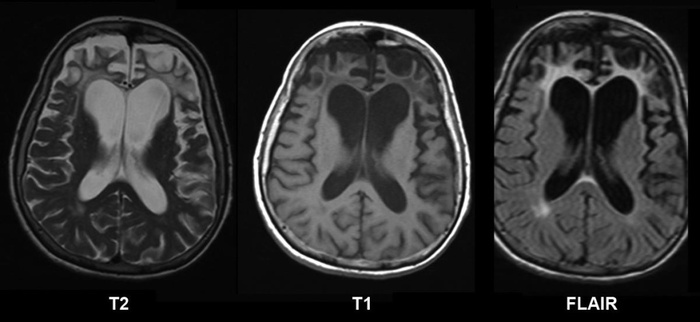

Антипсихотики вызывают структурные изменения в мозге (особенно при длительном воздействии), например уменьшение объема серого вещества и расширение желудочков головного мозга (косвенный признак атрофии):

- Через 17–27 месяцев провели МРТ и аутопсию (вскрытие) мозга.

- 211 пациентов с шизофренией наблюдались 7–14 лет с регулярными МРТ.

- Чем выше доза, тем быстрее уменьшался объем серого вещества.

- У пациентов, которые прекращали прием, потеря ткани замедлялась.

- У группы на оланзапине уменьшился объем серого вещества в префронтальной коре.

- Анализ 33 МРТ-исследований (3,307 пациентов).

Результат:

- Типичные антипсихотики (галоперидол) — сильнее всего снижали объем мозга.

- Атипичные (рисперидон, оланзапин) — слабее, но эффект был.